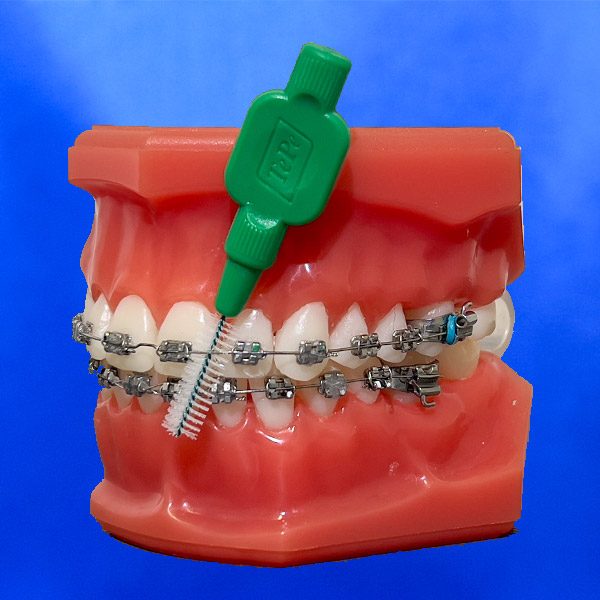

- Nur gründliches und regelmäßiges Zähneputzen mit einer fluoridhaltigen Zahncreme nach jedem Essen kann vor Zahnverfärbungen und Karies schützen.

- Die Zahnbürste ist das wichtigste Hilfsmittel bei der Zahnreinigung. Die Bürste sollte spätestens alle drei Monate ausgetauscht und zu den Kontrollterminen mitgebracht werden.

- Die Zwischenraumzahnbürste ist zur Zahnreinigung bei einer festen Klammer zusätzlich erforderlich.

- Eine Munddusche erleichtert das Entfernen von groben Speiseresten. Sie ist aber kein Ersatz für die Zahnbürste.